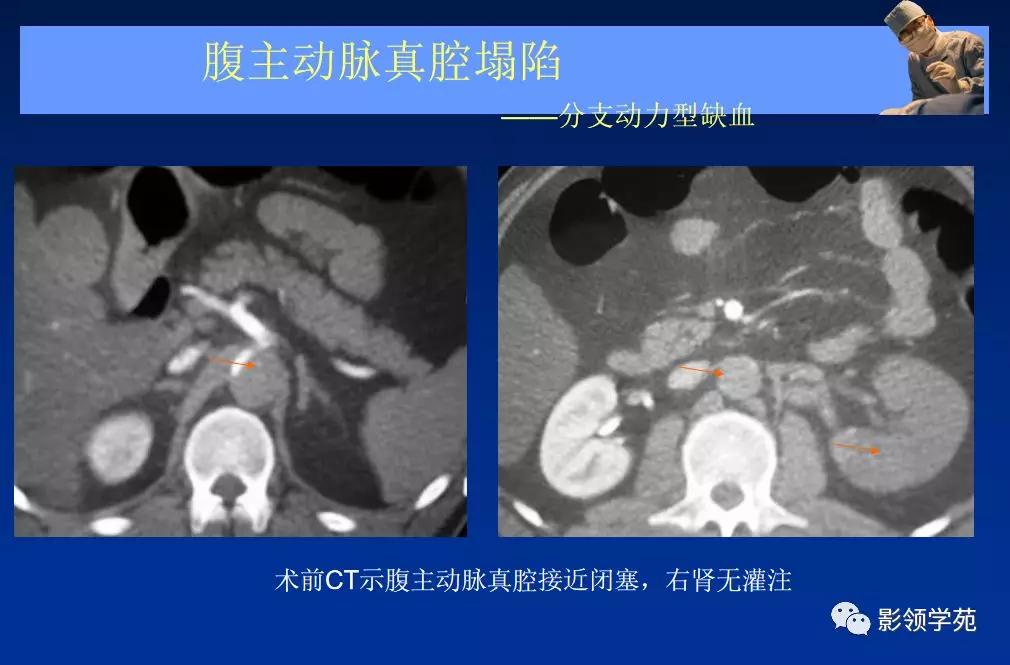

- 主动脉夹层(aortic dissection, AD)

- 真假“双腔” ,存在交通

- 远段同时存在再破口